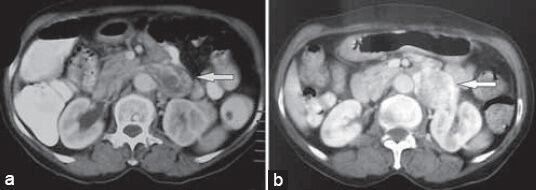

Tumors of vascular origin are unusual. These tumors are predominantly malignant and commonly arise from the inferior vena cava. Benign smooth muscle tumors arising from renal vein are very rare. We present a case of leiomyoma of renal vein in a post-menopausal woman that clinically resembled a retroperitoneal paraganglioma.